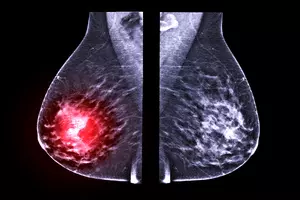

유방암 검사는 유방암을 진단하기 위한 중요한 검사이며, 유방 촬영술, 유방 초음파 검사, MRI, CT, 조직검사가 있습니다. MRI와 CT 검사는 금식이 필요하며, 검사 종류에 따라 금식 시간과 방식이 다릅니다. 유방 촬영술, 유방 초음파 검사는 금식이 필요하지 않습니다.